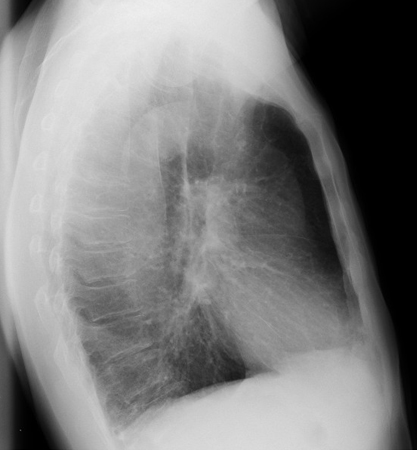

Radiografia torácica

Raramente diagnóstica, mas útil na exclusão de outras patologias e na avaliação da presença de comorbidades significativas (por exemplo, fibrose pulmonar, cardiomegalia).[1]

Pode-se verificar o aumento da proporção anteroposterior, do diafragma achatado, do aumento dos espaços intercostais e de pulmões hipertransparentes.[Figure caption and citation for the preceding image starts]: Radiografia torácica da doença pulmonar obstrutiva crônica (DPOC; vista anteroposterior): pulmão hiperinsuflado, diafragma achatado, aumento dos espaços intercostaisDo acervo de Manoochehr Abadian Sharifabad, MD [Citation ends].

[Figure caption and citation for the preceding image starts]: Radiografia torácica da DPOC (vista lateral): pulmão hiperinsuflado, diafragma achatado, aumento do diâmetro anteroposterior (tórax em tonel) na vista lateralDo acervo de Manoochehr Abadian Sharifabad, MD [Citation ends].

Pode também demonstrar complicações da DPOC, como pneumonia e pneumotórax.

hiperinsuflação